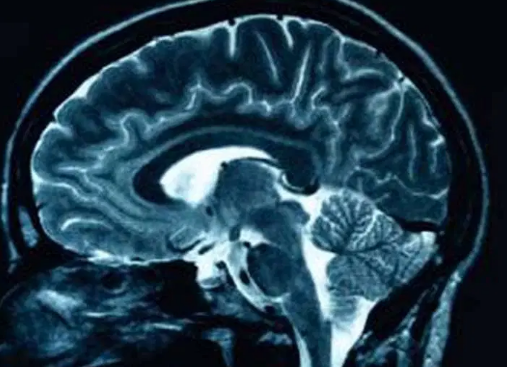

A comprehensive report from the Substance Abuse and Mental Health Services Administration (SAMHSA) indicates that stimulant medications, often prescribed for ADHD, interact with the brain’s neural pathways. This interaction may alter the risk profile for developing co-occurring mental health issues, which warrants careful management and monitoring of ADHD treatments.

The mechanisms by which ADHD affects long-term health are complex. The condition impacts executive functions, which govern impulse control, emotional regulation, and planning. Dysfunction in these areas can lead to lifestyle patterns that increase health risks.